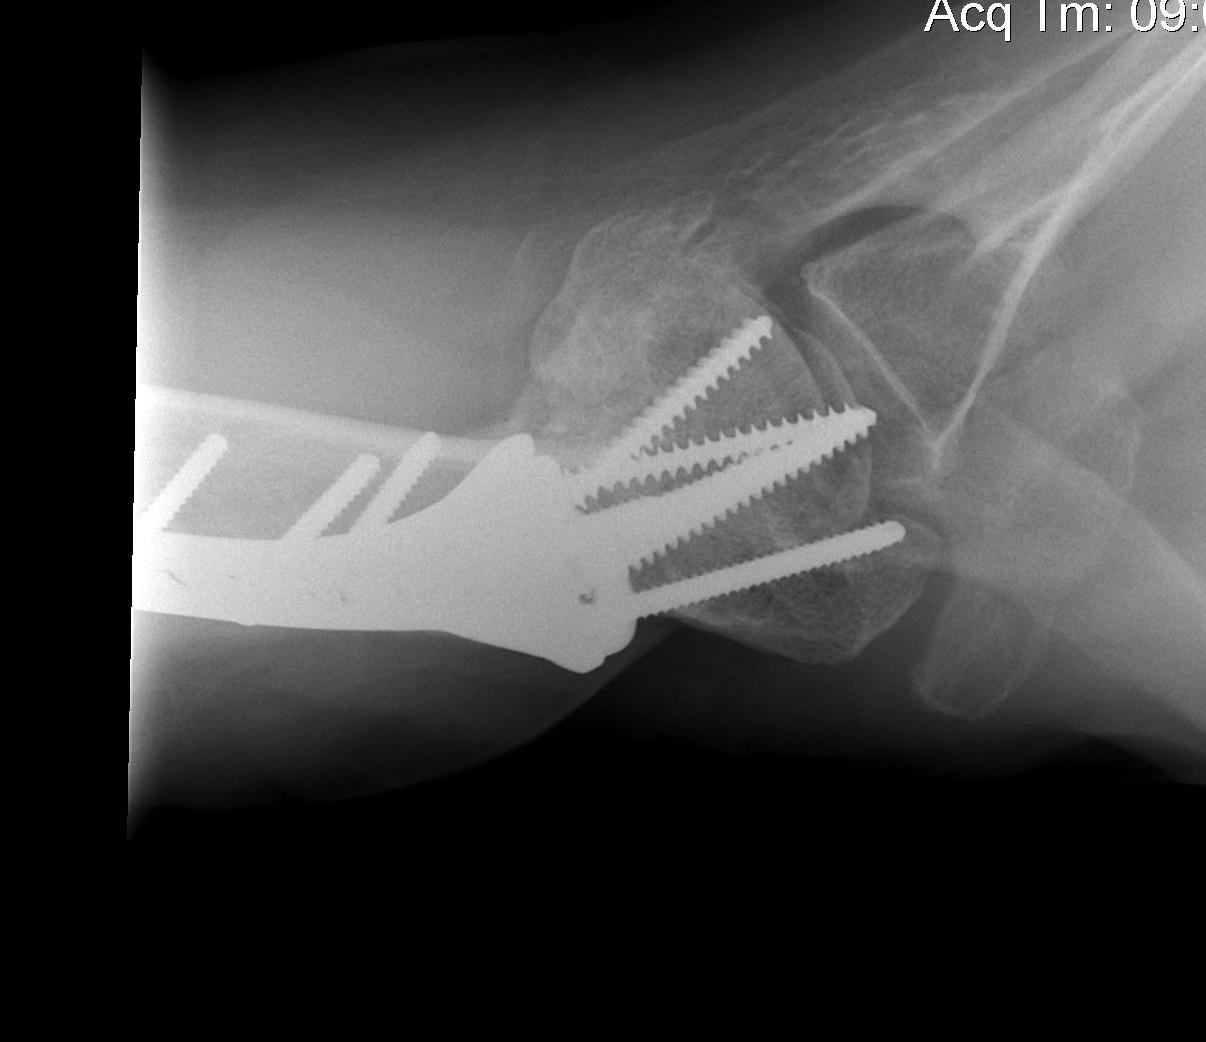

proximal humerus fracture Background ORIF with locking plate Arthroplasty Greater tuberosity fractures Lesser tuberosity fractures / avulsions Book traversal links for Proximal humerus fractures ‹ Pectoralis Major Tears Up Background ›